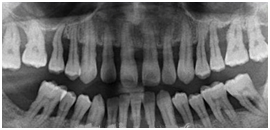

患者女性,59歲,右側(cè)后牙咀嚼無(wú)力,刷牙時(shí)牙齦出血。無(wú)系統(tǒng)性疾病??谇粰z查顯示全口多數(shù)牙牙石(++),牙齦紅腫,探診出血,牙周袋袋深4——6mm,右下后牙有Ⅰ——Ⅱ度松動(dòng),X線(xiàn)片如圖所示: